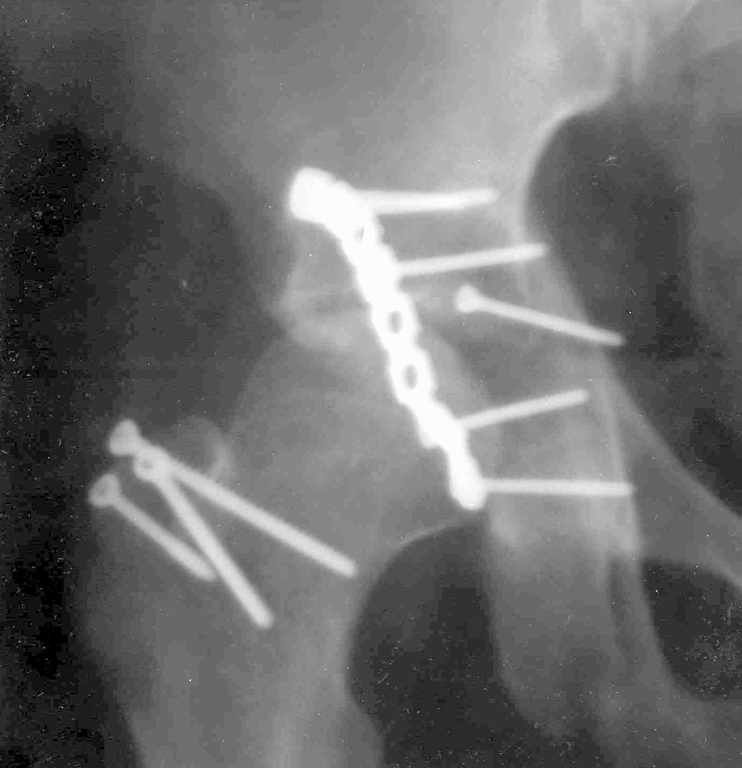

XrayCTРезультат повторной операции

В нашей клинике 23.04.03 руководитель центра А.В. Рунков выполнил выездную показательную операцию. Не смотря на то, что с момента травмы прошло 2 месяца отломки вертлужной впадины были репонированы, восстановлена конгруэнтность суставных поверхностей тазобедренного сустава, фиксация реконструктивной пластиной. Операция была выполнена на высочайшем профессиональном уровне и её результат превзошёл мои ожидания.Ранний послеоперационный период протекает без осложнений, больной "воспрял духом", чувствует себя хорошо, занимается ЛФК, разработкой движений в коленном и тазобедренном суставах, сидит, ходит на костылях. На мой взгляд представленный случай является ярким примером целесообразности телеконференций, позволяющим достичь конкретного результата. Особую благодарность хочется выразить Александру Челнокову - организатору Форума. С Уважением Андрей Стасюк